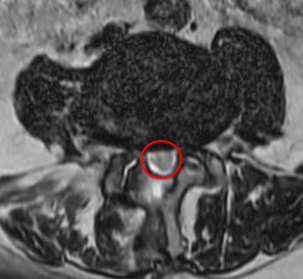

治療後

また術後の腰椎MRIで脊柱管狭窄症のあったL4/5の箇所が減圧されている所見を認めました。現在は、もともとあった右下肢の痛みと痺れ、腰痛はなくなり、「痛みを気にすることなく趣味の絵描きができるようになった」とお話しされていました。